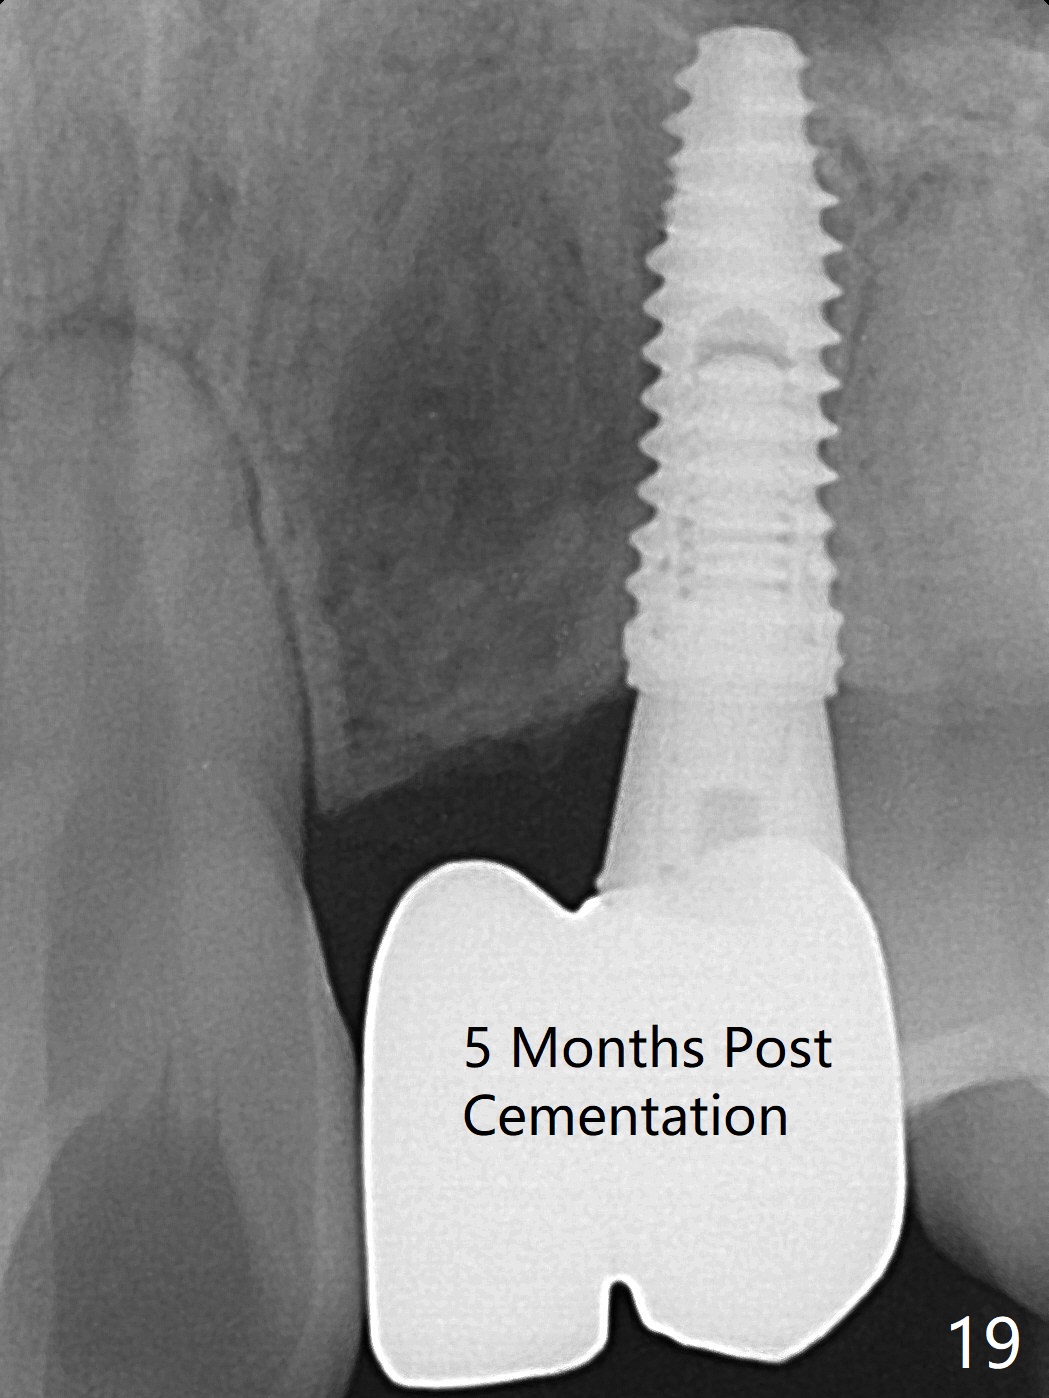

18岁男从外州大学回来,无症状,但是6号牙(右上尖牙)颊侧瘘道(图一,二(角化龈充分(箭头))),根尖片显示植体近中骨吸收(图三:*),而对侧植体仿佛骨整合(图四)。患侧切开后发现植体颊侧暴露,松动。拔除后骨缺损由粘性骨粉修复(图七,九:*),覆盖PRF膜(图七:P)和带钛网(图九:^)不可吸收膜(图五-七),后者用两个小钉子固定(图六(腭侧),七(颊侧),九),使用新的刀片和一个特殊尖头剥离器在颊侧骨膜下相当广泛分离,使用PTFE缝线,粘膜下水平褥式缝合之后(图八:箭头),多个垂直间断缝合,两个乳头垂直褥式缝合。术后一周伤口没有裂开,术后疼痛肿胀已经消退(图十)。术后十八天牙槽嵴仿佛比对侧还要宽(图十一,三与图十二,四(取模)对比)。术后5.5个月伤口没有裂开,牙槽骨,角化龈宽(图十六),与钛网和两个小钉子固定有关(图十五,十七)。CT显示牙槽骨只能容纳2.5或者3.0毫米植体(图十八)。11号牙植体牙冠粘固后没有骨质吸收(图十九),其实10,11号牙颊侧骨板隆起(图二十至二十二),而6植体失败,颊侧骨板吸收,甚至累及5号牙(图十七)。